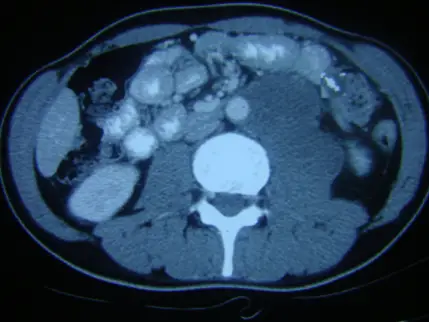

下圖為中年男性所呈現的後腹膜腔腫瘤,最不可能的診斷為:

橫斷面增強CT顯示右側後腹膜大範圍均質軟組織密度團塊,邊界稍清楚,與腰大肌緊鄰,但無明顯大範圍壞死或囊化。腫瘤增強後呈輕度至中度均質增強,並包裹主動脈與下腔靜脈,表現如「漂浮主動脈」現象,典型於淋巴瘤病灶;未見脂肪成分或鈣化,也無顯著侵蝕性骨改變。